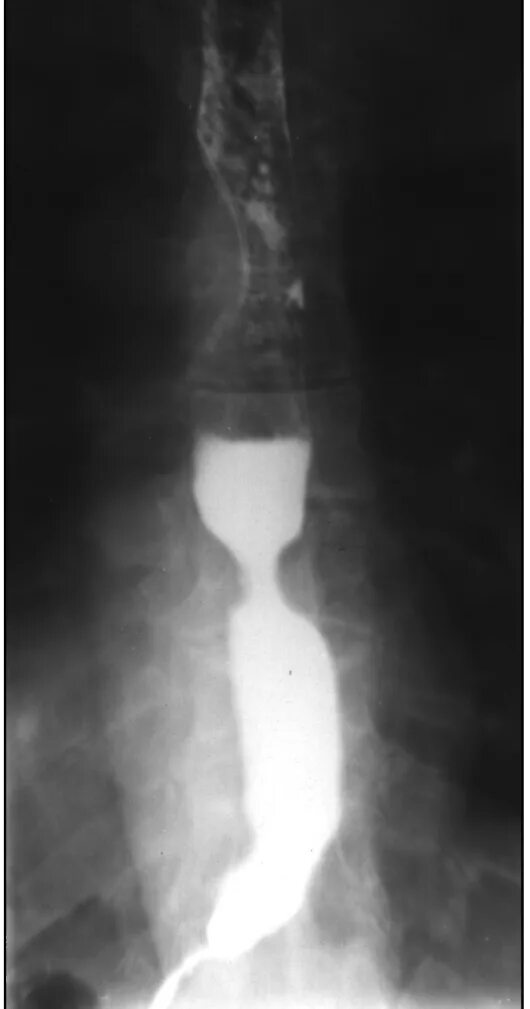

Дисфагия пищевода рентген. контрастирование пищевода барием. контрастирование пищевода рентген. рентген пищевода при стриктуре.

Пептическая язва пищевода рентген. контрастирование пищевода рентген. гэрб стриктура пищевода. рентгенодиагностика стриктур пищевода.

Рентгенологическое исследование пищевода с бариевой взвесью. контрастирование пищевода рентген. патология пищевода на рентгене. двойное контрастирование пищевода.